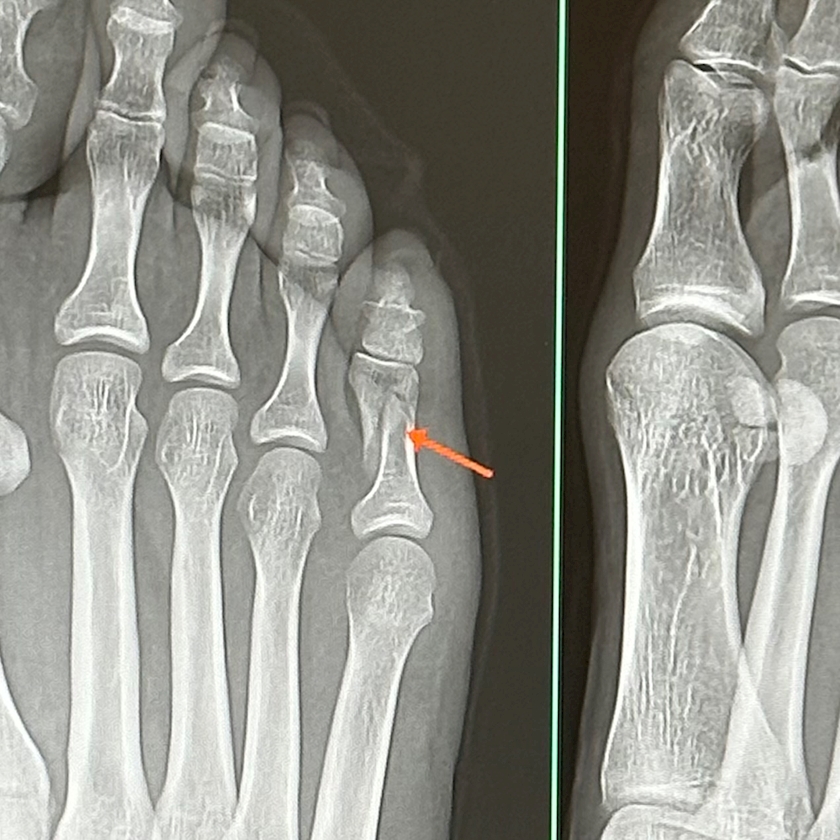

23歳はじめての骨折

笑ってください

23にもなって裸足で店歩いてぶつけて骨折なんて

恥ずかしくてたまりません

あんなに裸足危ないよと言われていたのに

レントゲンの写真撮ろうとしたら

丁寧に矢印まで付けてくれた

綺麗な骨